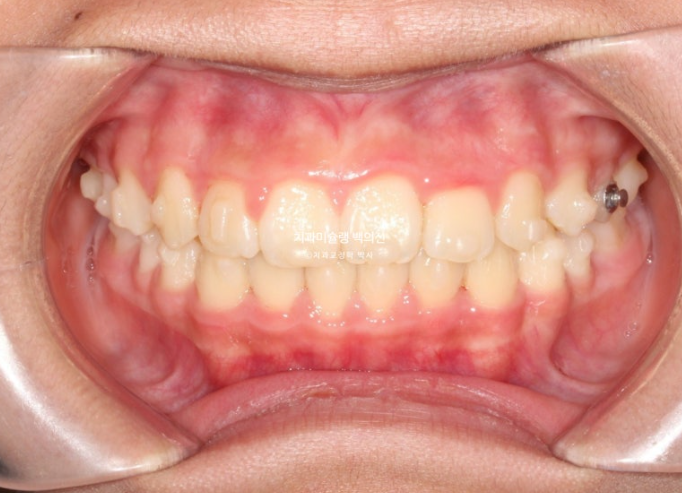

이제 전후비교 보겠습니다.

총 치료기간은 1년 6개월이며 중간에 중심선 이슈로 잠시 쉬는 시간이 4개월 있었습니다.

재제작은 총 2회 했습니다.

24.02~25.07

치료결과가 어린이 교정이 아닌, 정식 성인교정 치료 결과에 준하는 만큼 유지장치도 철저하게 들어갑니다.

어긋난 중심선이 맞아졌으며 기울어진 앞니 치축도 좋아졌습니다.

앞니가 깊게 물리는 과개교합도 좋아졌습니다.